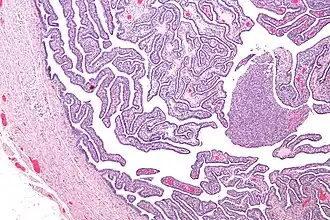

Eileiderontsteking of salpingitis is een ontsteking van de eileider(s), die vroeger ook wel salpingen werden genoemd.

Het gaat meestal om micro-organismen die via de vagina en de baarmoederhals in de eileiders en de buikholte zijn gekomen. De aandoening kan zowel sluipend als heftig verlopen, met zeer hevige pijn en hoge koorts. Behandeling is met geëigende antibiotica en eventueel, bij abcesvorming, chirurgisch. Als de eileider zelf met pus is gevuld spreekt men van een pyosalpinx.